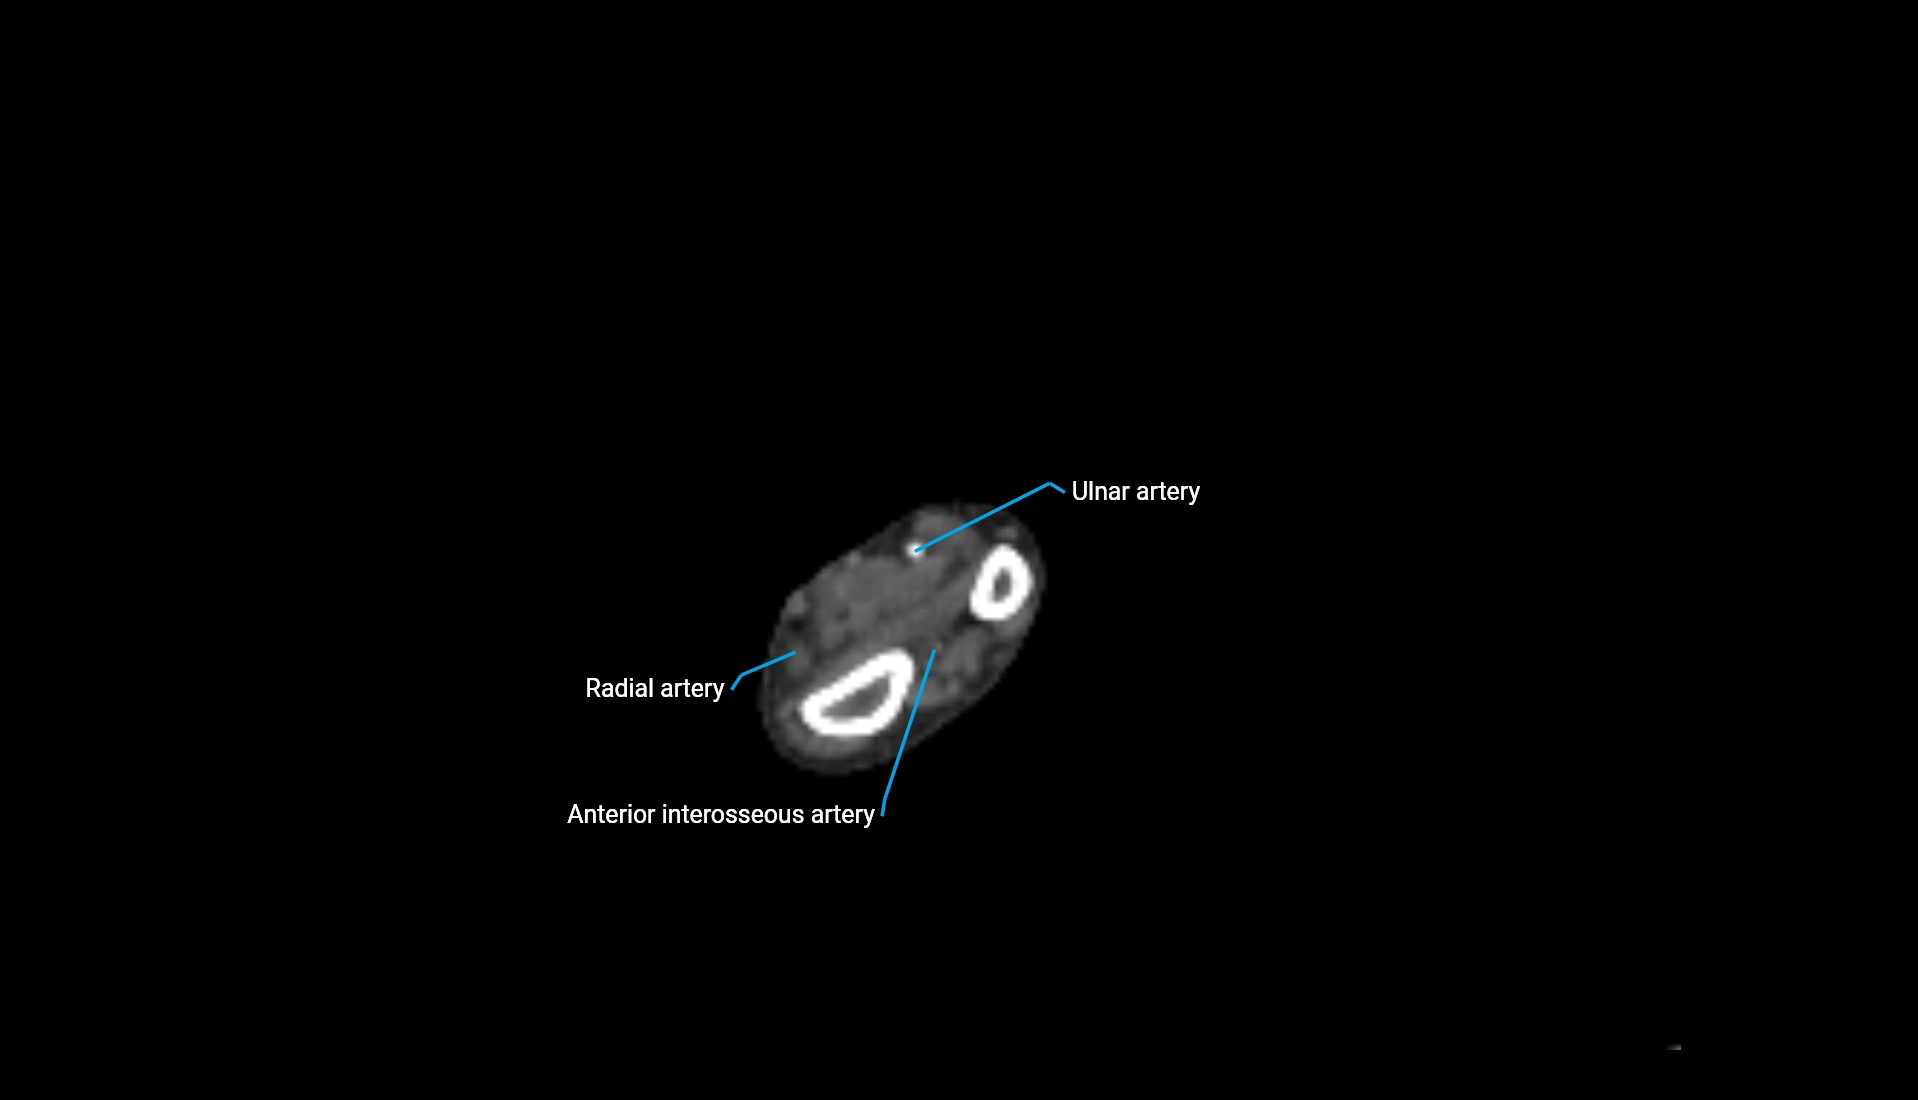

CT Appearance

Non-Contrast CT:

• Cortex: High-density, sharply defined

• Subchondral bone: Dense cancellous matrix

• Articular surface: Smooth concave contour articulating with the capitellum

• Excellent for evaluating bone integrity, alignment, and subtle fractures